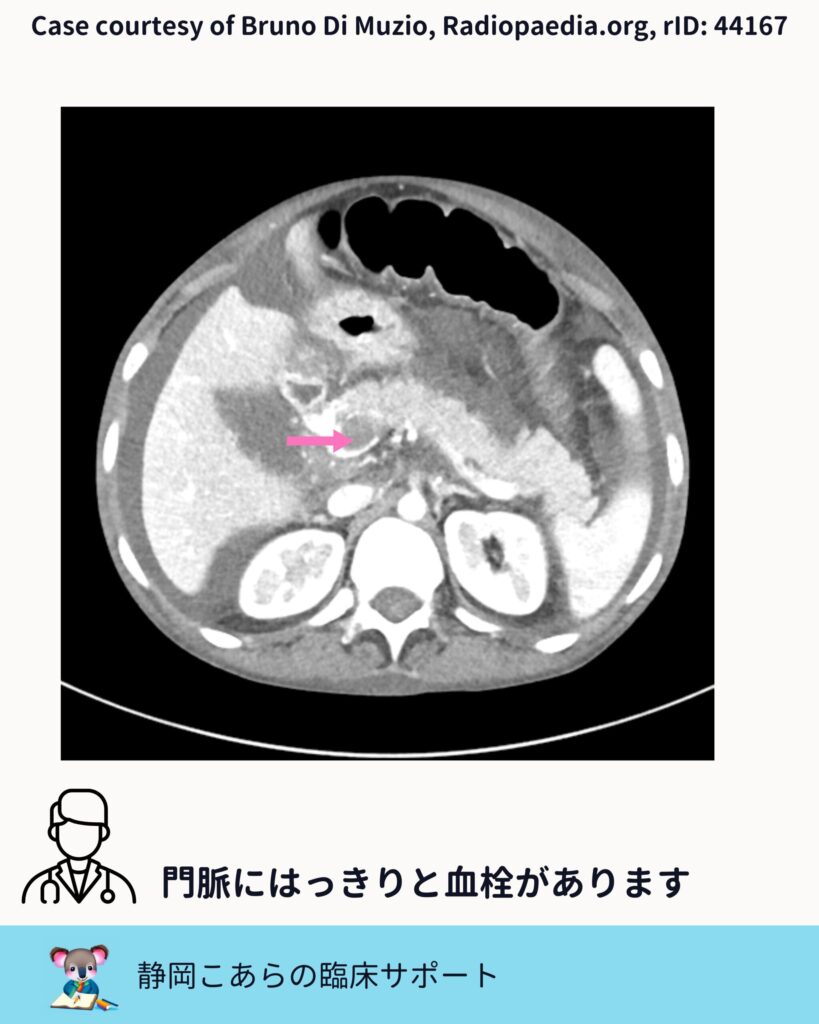

門脈血栓をどう見るか

今回の症例では、門脈内に造影欠損が認められます。スライスを追うと、はっきりとした血栓として確認できます。

門脈血栓症では、 ・門脈の拡張 ・造影欠損 ・側副血行路の有無

こうした点をセットで評価していくことが、臨床的には自然です。